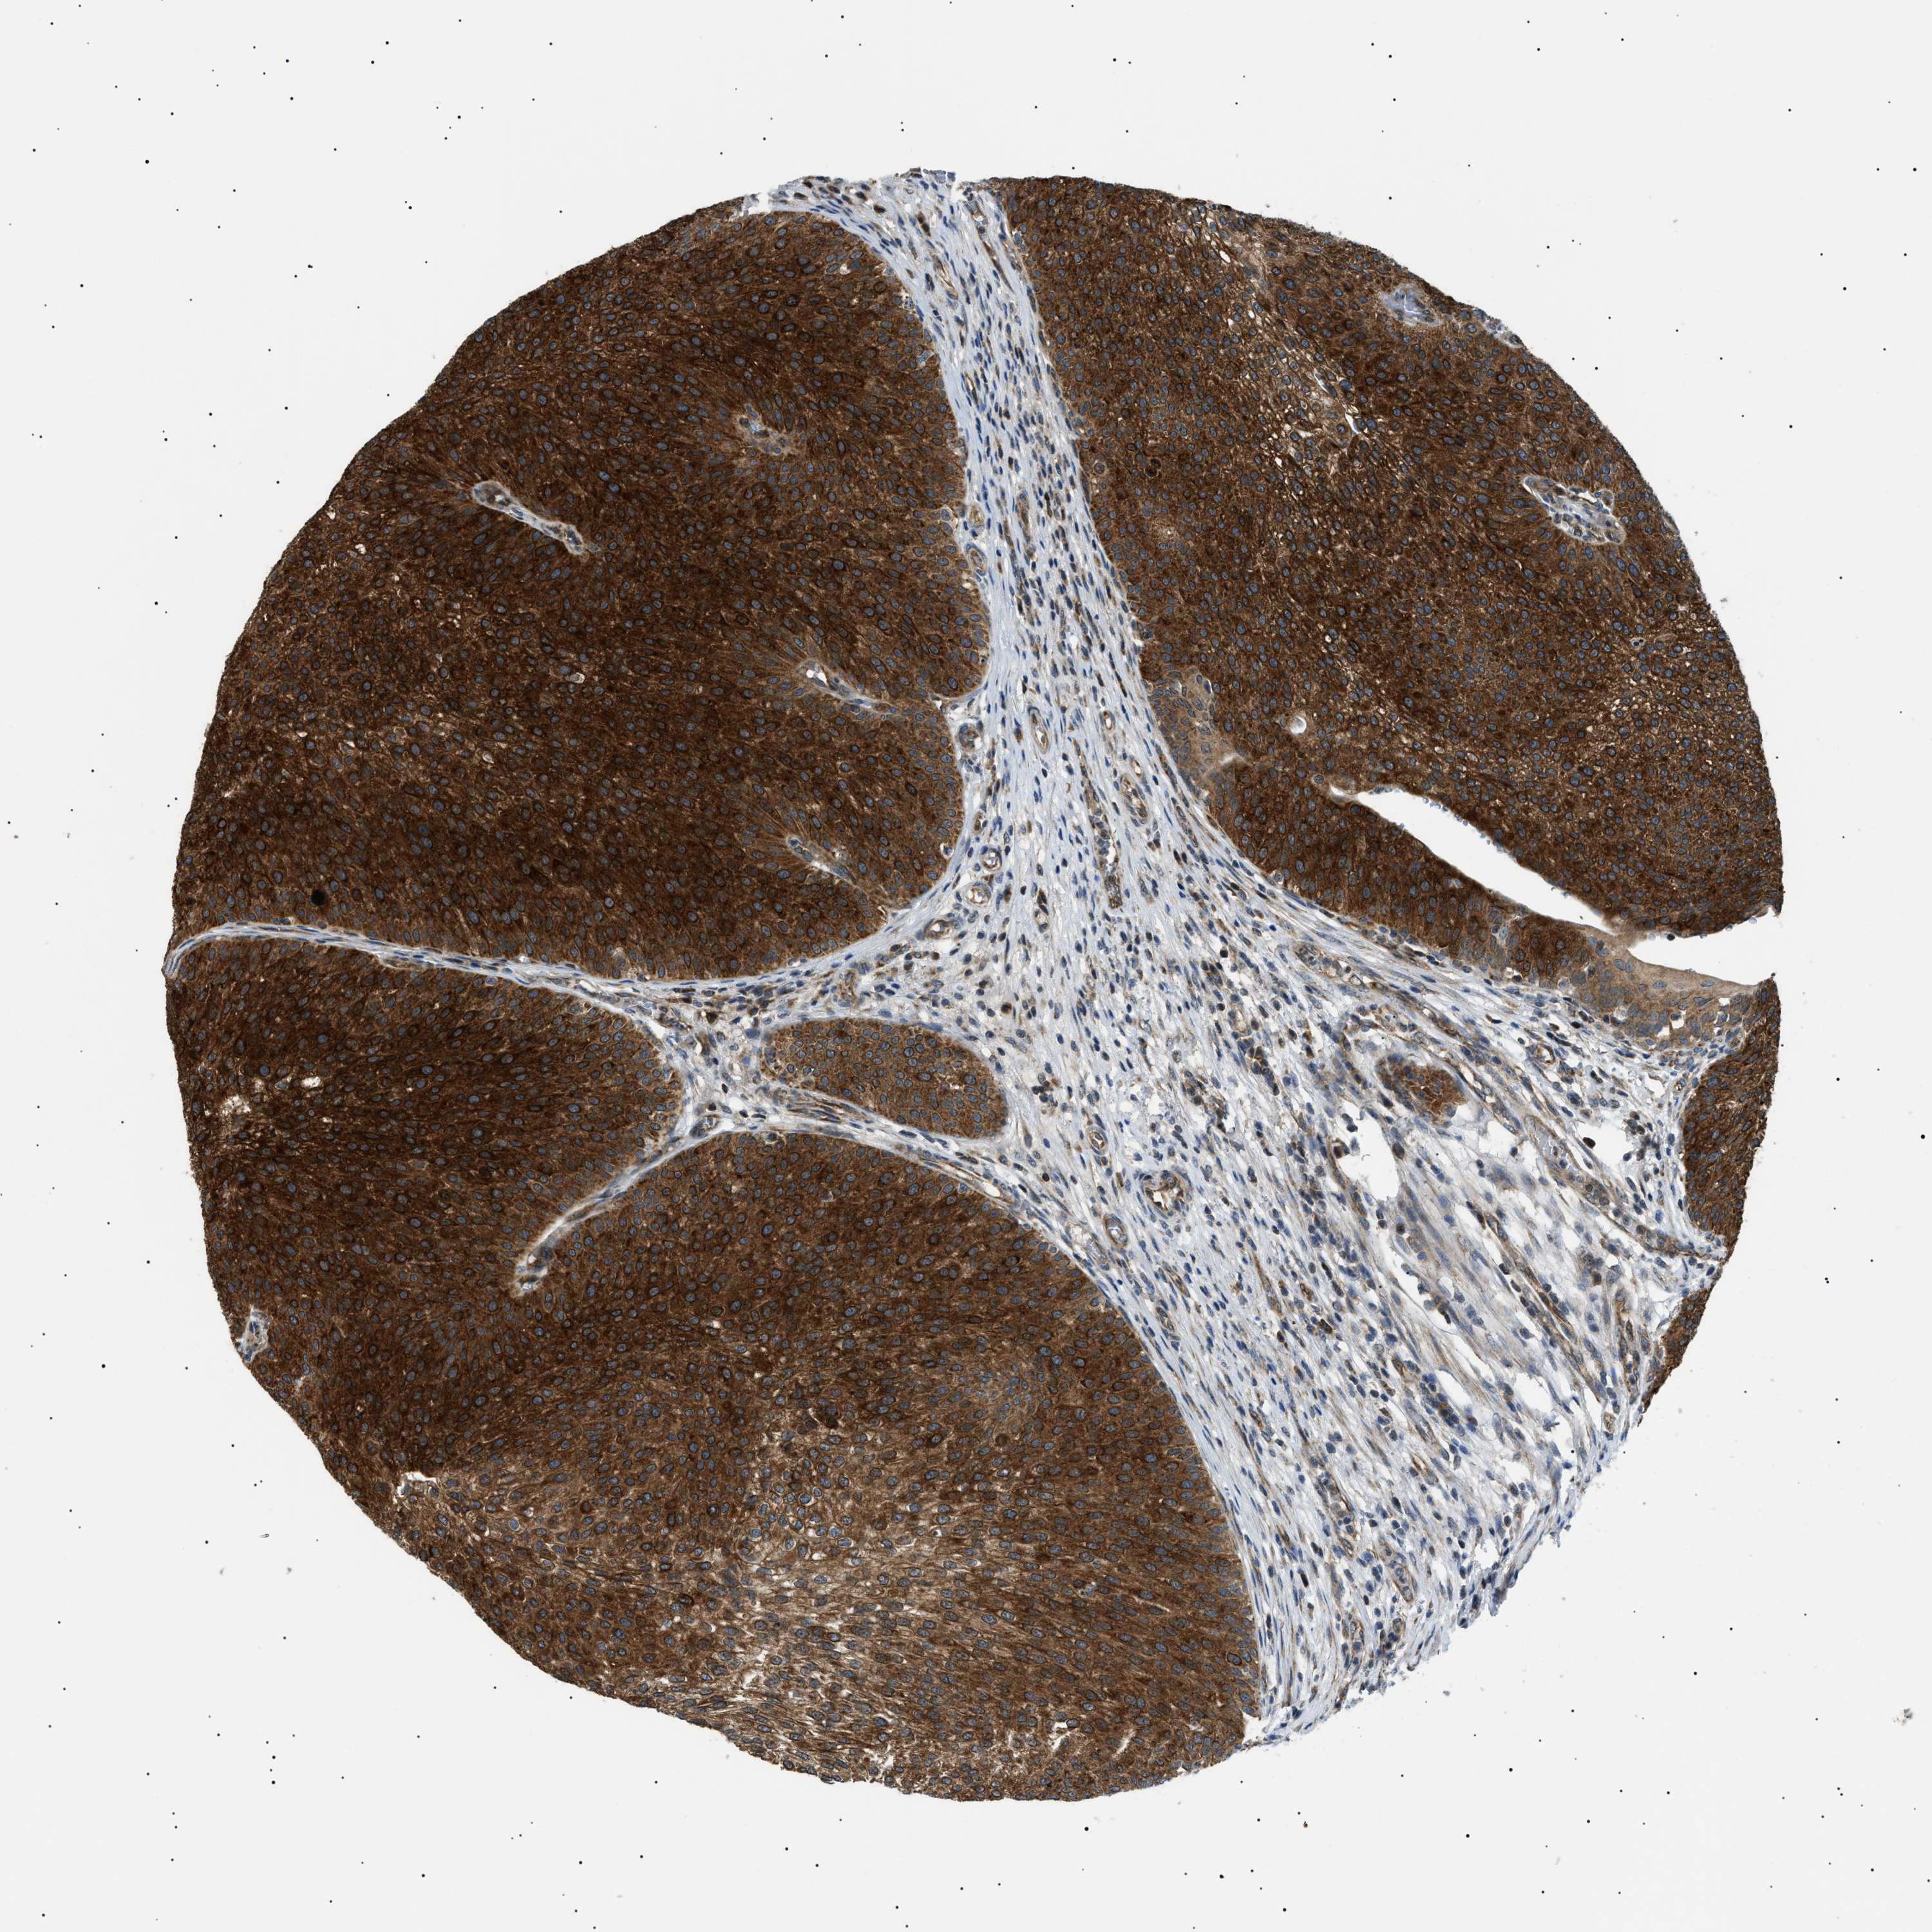

UROTHELIAL CANCER - Protein expressioni

A mouse-over function shows sample information and annotation data. Click on an image to view it in a full screen mode. Samples can be filtered based on level of antibody staining by selecting one or several of the following categories: high, medium, low and not detected. The assay and annotation is described here.

Note that samples used for immunohistochemistry by the Human Protein Atlas do not correspond to samples in the TCGA dataset.

Antibody stainingi

Antibody staining in the annotated cell types in the current human tissue is reported as not detected, low, medium, or high, based on conventional immunohistochemistry profiling in selected tissues. This score is based on the combination of the staining intensity and fraction of stained cells.

Each image is clickable and will lead to virtual microscopy that enables deeper exploration of all samples and also displays staining intensity scores, fraction scores and subcellular localization as well as patient and tissue information for each sample.

Antibody HPA016431

Staining

High

Medium

Low

Not detected

Intensity

Strong

Moderate

Weak

Negative

Quantity

>75%

75%-25%

<25%

None

Location

Nuclear

Cytoplasmic/membranous

Cytoplasmic/membranous,nuclear

Urothelial carcinoma, Low grade

Urothelial carcinoma, High grade